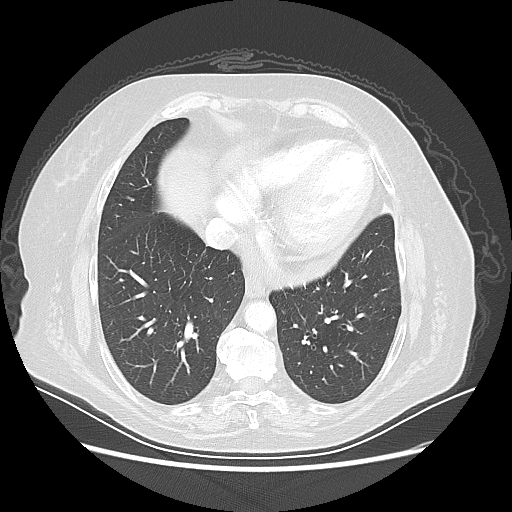

Original NATIVE CT scan (input)

Full window (WL 1023.5, WW 4095 β†’ Low βˆ’1024, High +3071)

Lung window (WL -600, WW 1500 β†’ Low βˆ’1350, High +150)